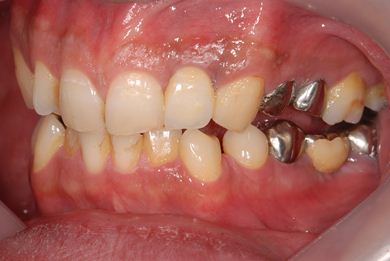

抜歯即日スピードインプラント治療

| 性別/年齢 | 男性 / 36歳 | ||||||||||||||||||||||||||||||||

| 主訴 | 前歯が折れていてないので、インプラント治療を希望。 | ||||||||||||||||||||||||||||||||

| 治療内容 | インプラント1本(抜歯即日スピードインプラント)、ハイブリッドセラミッククラウン1本 | ||||||||||||||||||||||||||||||||

| 総治療費 | 257,250円 | ||||||||||||||||||||||||||||||||

| 治療期間 | 7ヶ月 |